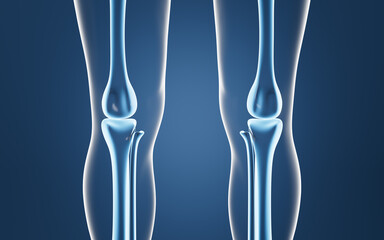

Podobny obraz Medical Elbow Anterior View X-Ray Radiograph Illustrating...